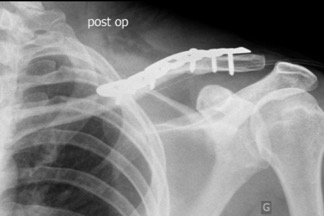

L'intéret de cette opération est de diminuer la déformation ou le risque de non consolidation de l’os (pseudarthrose) et parfois meme de permettre une récupération plus précoce. Le chirurgien va devoir ouvrir votre peau, remettre les morceaux d'os en face les uns des autres (réduction de la fracture) et les fixer ensemble (stabilisation) pour qu’ils ne bougent plus. On parle de synthèse de clavicule. Il met en place le plus souvent une plaque avec des vis. Votre os mettra 9 semaines pour se consolider.

L’opération consiste globalement à venir fixer les fragments de la clavicule qui sont séparés par la fracture, à redonner à votre clavicule une forme proche de celle qu'elle avait avant de se casser. Une plaque est placée généralement en avant ou au-dessus de la clavicule, et les fragments sont fixés à cette plaque par des vis. Une fois la réparation terminée (synthèse) la peau est fermée, parfois sur un petit tuyau aspirant l’hématome postopératoire.

Le but de cette chirurgie est de restaurer la forme de votre clavicule avec une consolidation dans les délais classiques de neuf semaines. Une cicatrice sera bien sur visible.

Dans la grande majorité des cas, les résultats sont très bons. Il n’est pas rare d'avoir à retirer la plaque qui peut devenir génante sous la peau.

| Radiographie pré opératoire | Radiographie post opératoire | Cicatrice cutanée |